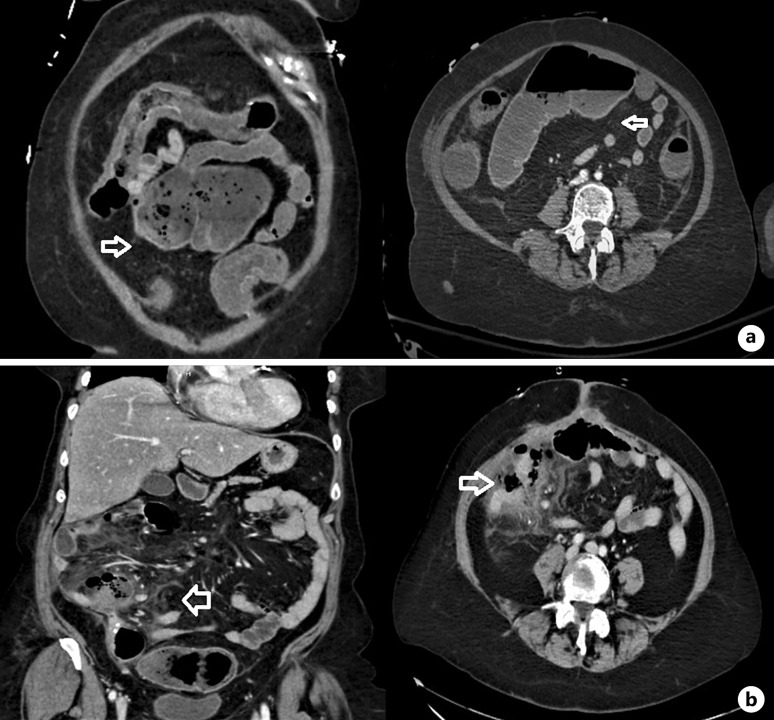

Case presentation: An 86-year-old woman presented to the emergency department (ED) with abdominal pain after a mild COVID-19 infection. She was admitted with ischemic colitis, but conservative treatment failed. In the operating room, her entire colon was found to be ischemic, necessitating a total colectomy with end ileostomy. Nine months later, she returned to the ED with mild respiratory symptoms and severe right upper quadrant pain. Imaging revealed pneumoperitoneum and a mid-abdominal abscess. An emergency laparotomy revealed small bowel perforation, with final histology confirming ischemia. The patient had received three doses of the COVID-19 vaccine and was on therapeutic anticoagulation for a history of pulmonary embolism.